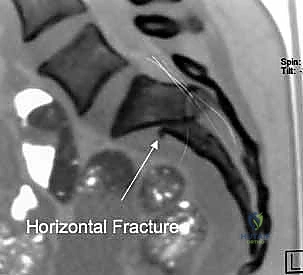

3. التصوير المقطعي المحوسب (CT Scan): وهو المعيار الذهبي (Gold Standard) لتشخيص كسور الحوض والعجز. يقوم الدكتور هطيف باستخدام تقنية إعادة البناء ثلاثي الأبعاد (3D Reconstruction) لفهم هندسة الكسر بدقة متناهية قبل الدخول إلى غرفة العمليات.

يمر عبر عظم العجز جذور الأعصاب العجزية التي تتحكم في وظائف حيوية مثل حركة الأطراف السفلية، التحكم في المثانة، ووظائف الأمعاء. أي انزياح عظمي في هذه المنطقة قد يؤدي إلى قطع أو انضغاط هذه الأعصاب، مما يسبب إعاقة دائمة إذا لم يتم تحريرها وتثبيت الكسر بدقة متناهية بواسطة خبير مثل الأستاذ الدكتور محمد هطيف.

يرتبط العجز بعظام الحرقفة عبر المفصل العجزي الحرقفي (Sacroiliac Joint)، وهو مفصل مدعوم بشبكة من أقوى الأربطة في جسم الإنسان. أي كسر أو خلع في هذا المفصل أو في عظم العجز يؤدي إلى فقدان الاستقرار الميكانيكي للجسم بالكامل.